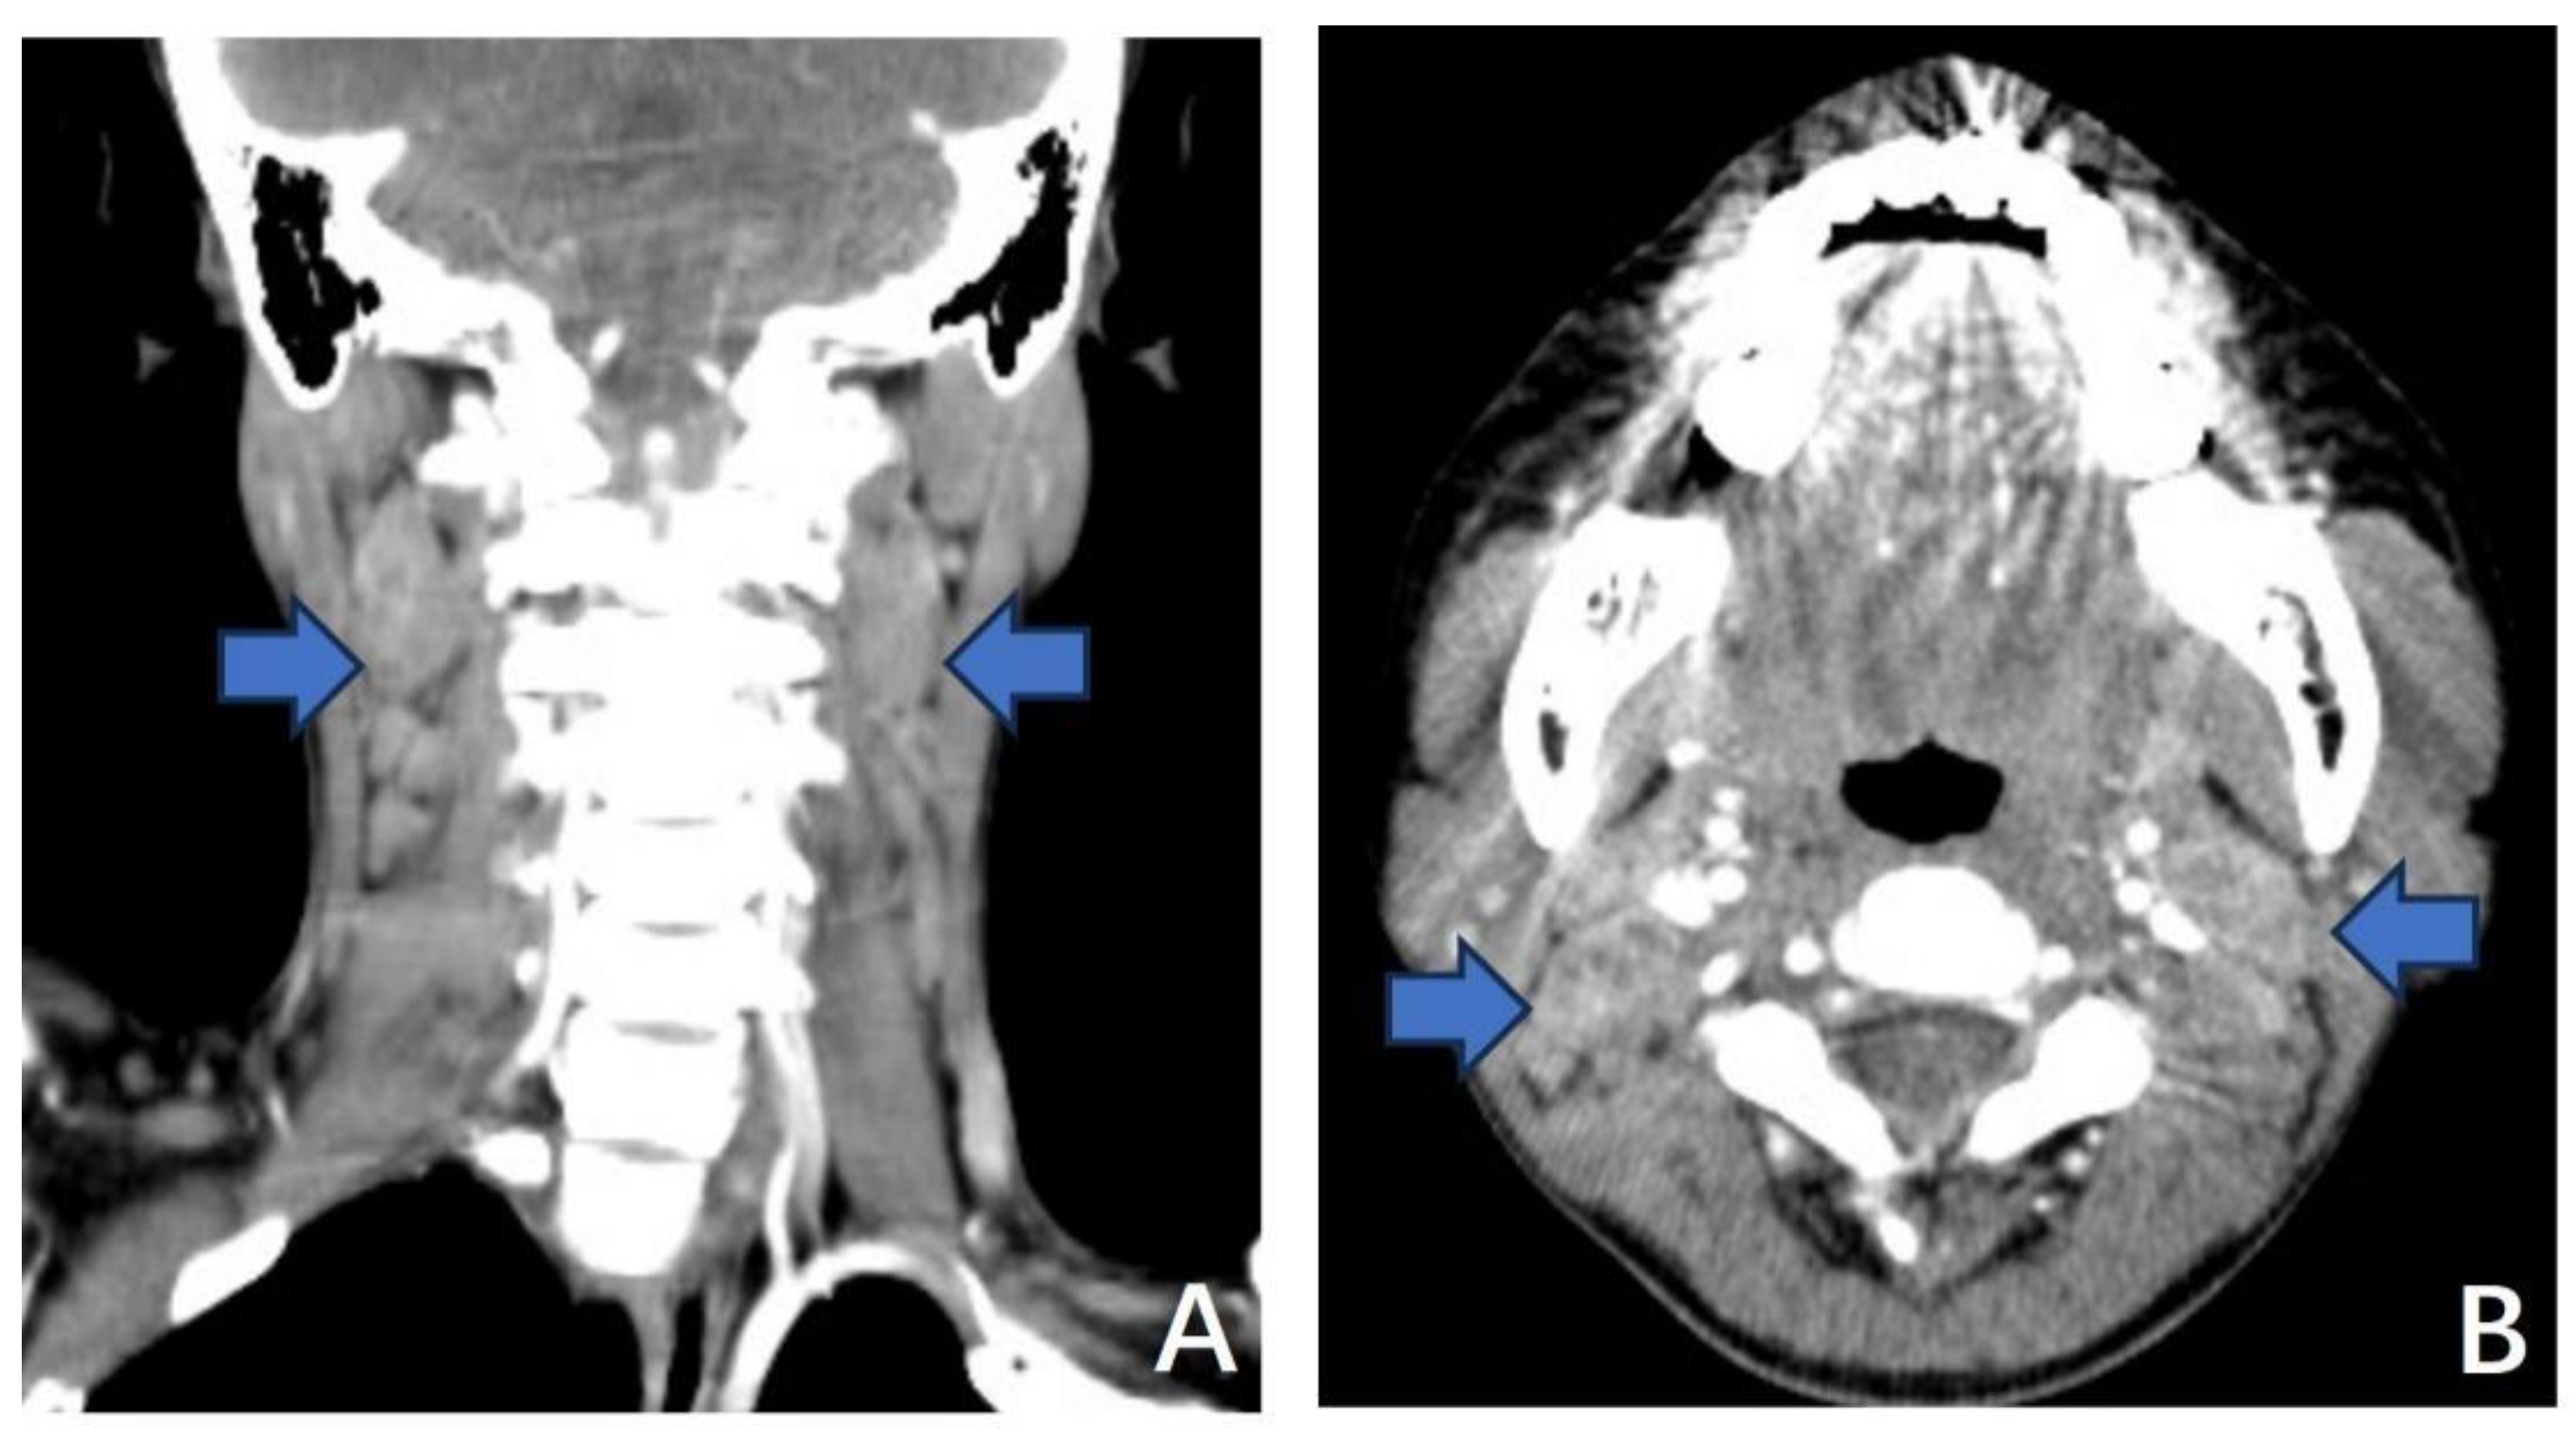

3.1.1. Case 1